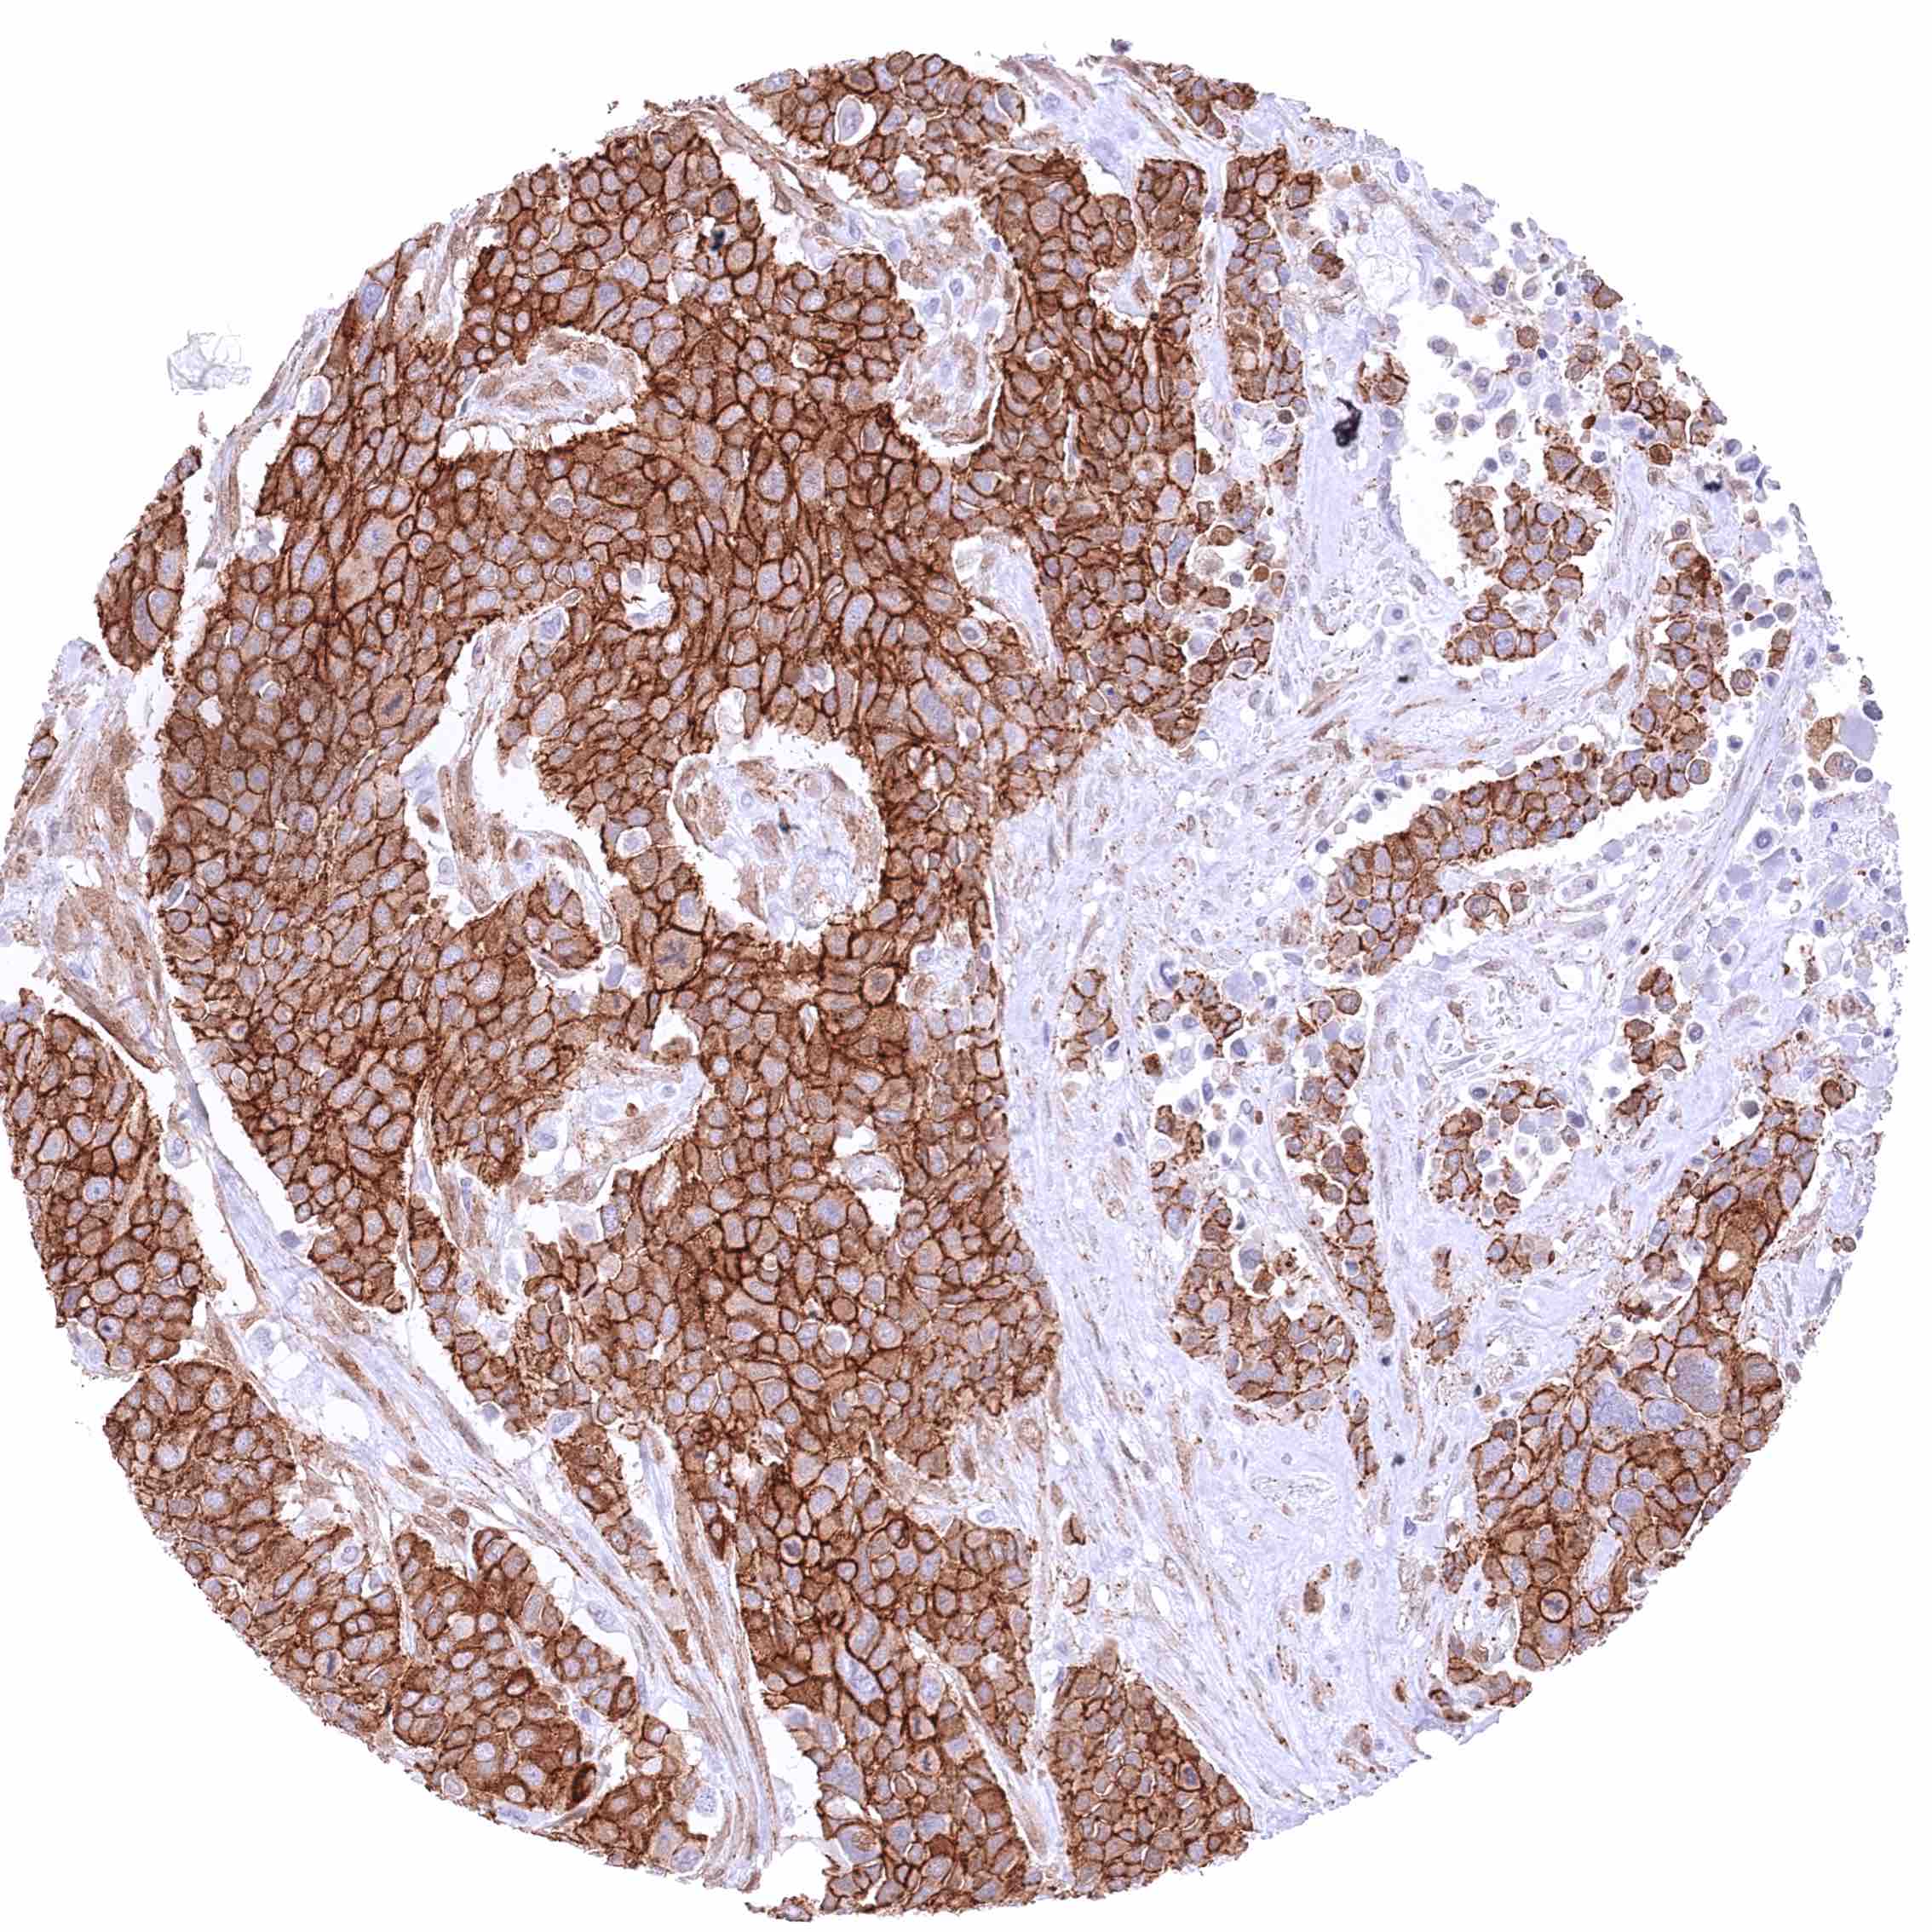

Urinary bladder – Muscle-invasive urothelial carcinoma with strong cytoplasmic and often also nuclear β-Catenin staining of tumor cells.

Uterus, cervix – Squamous cell carcinoma with strong membranous β-Catenin positivity of tumor cells.

Uterus, cervix – Squamous cell carcinoma with strong membranous β-Catenin staining of tumor cells. There might be an additional slight cytoplasmic staining in this case.